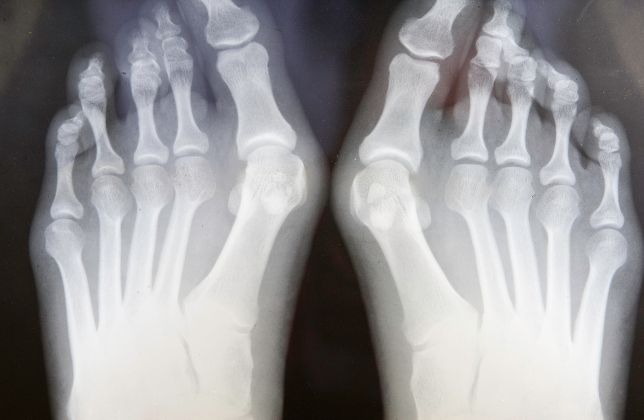

Hallux Valgus (Juanete)

El hallux valgus, comúnmente conocido como juanete, es una deformidad en la que el dedo gordo del pie se desvía hacia los otros dedos, formando una protuberancia en la base del dedo.